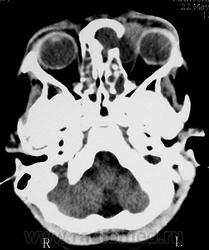

Орбитальная патология. Черепно-мозговые грыжи. +

Фронто-орбитальное энцефалоцеле